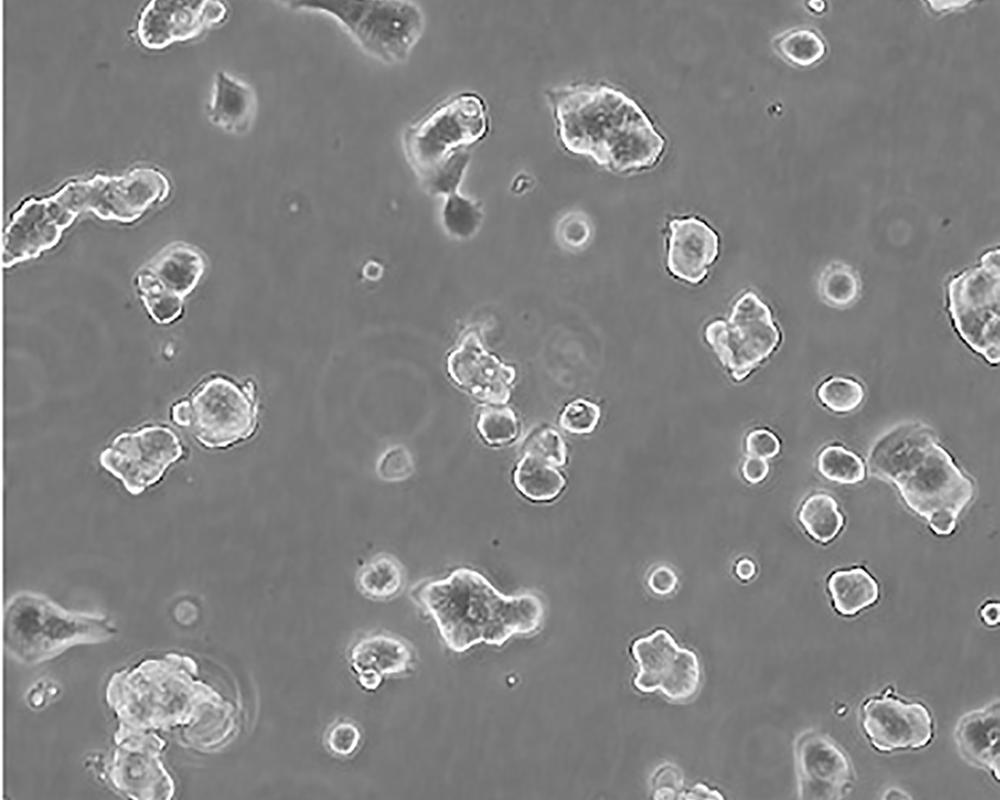

ZR-75-1 [ZR751]

中文名稱 人乳腺癌細(xì)胞

組織來源 浸潤性導(dǎo)管癌;腹水轉(zhuǎn)移;女性

生長特性 adherent

形態(tài)特征 epithelial

細(xì)胞描述 該細(xì)胞產(chǎn)生高水平的黏液素MUC-1 mRNA,低水平的MUC-2 mRNA,但不表達(dá)MUC-3基因;表達(dá)雌激素受體。